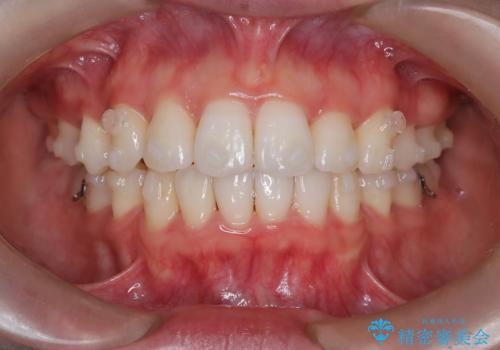

【抜歯インビザ】凸凹を綺麗になおしたい

- 前歯の凸凹を主訴に来院されました。

叢生量が多いため、抜歯が必要となるため、ワイヤー矯正をお勧めしましたが、患者さんの希望によりインビザラインで治療を開始しました。途中でワイヤーリカバリーを必要とせず終了でき患者さんには満足していただけました。

ワイヤー矯正よりも期間がかかっています。